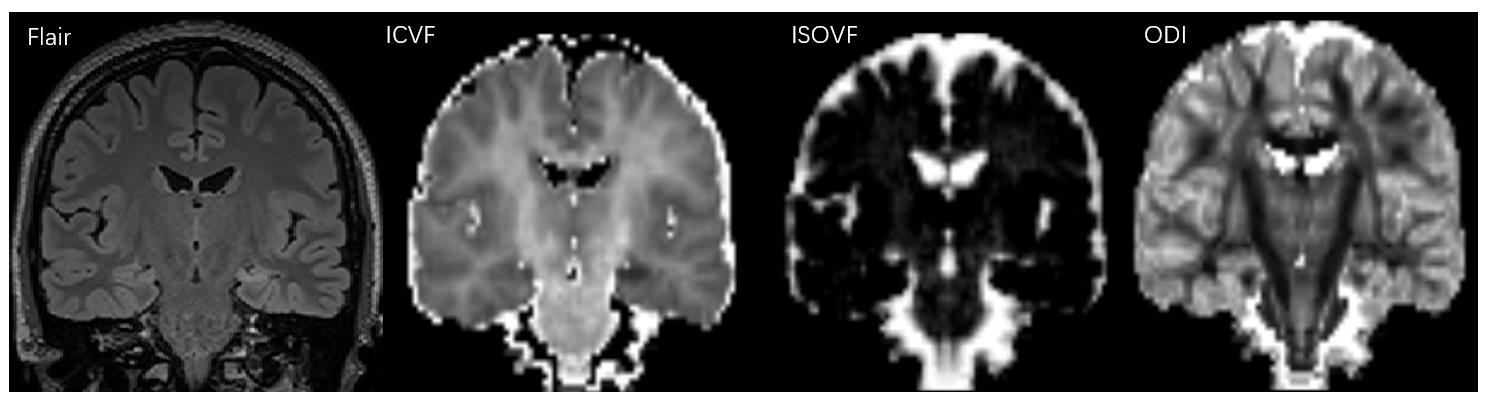

Compared with the contralateral and HC, the ipsilateral had significantly lower ICVF and ODI and significantly higher ISOVF (all P<0.05). Compared with the HC, the ISOVF was higher in the contralateral (P<0.05). For Flair signal intensities, the difference was significant between ipsilateral and HC (P<0.05). The detailed results are shown in Table 1. Between the ipsilateral and HC, Flair had moderate (area under curves, AUC=0.660) and parameters from NODDI model had high diagnostic performances (AUCs = 0.824 ~ 0.931), and logistic regression model combined ISOVF, ICVF, ODI (combinedNODDI model) had the best performance (AUC=0.970), as shown in Table 2 and Figure 2(a). Between the ipsilateral and contralateral, ISOVF, ICVF and ODI all had high diagnostic performances, with AUCs ranging from 0.723 to 0.908, and the AUC of the best combinedNODDI model was 0.962, as shown in Table 3 and Figure 2(b). Between the contralateral and HC, ISOVF had moderate diagnostic performances (AUC= 0.653), as shown in Figure 2(c). Based on the Delong test, the combinedNODDI model achieved a significantly higher diagnostic performance in differentiating ipsilateral from contralateral hippocampus and HC compared with all other single parameters (all p<0.05).

Fig. 2. ROC curves of the ICVF, ODI, ISOVF, Flair and combined NODDI models for distinguishing Ipsilateral and HC(a). ROC curves of the ICVF, ODI, ISOVF, and combined NODDI models for distinguishing Ipsilateral and Contralateral(b). ROC curves of the ISOVF for distinguishing Contralateral and HC(c). ISOVF = isotropic volume fraction; ICVF = intracellular volume fraction; ODI = orientation dispersion index.